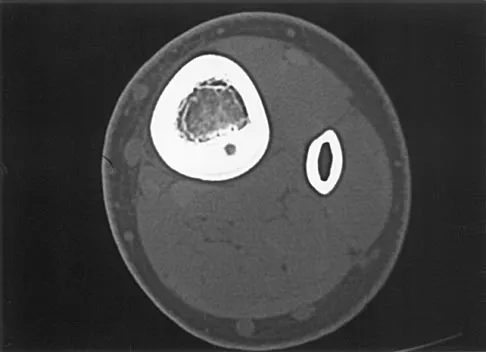

Question 13

A 7-year-old boy has had chronic left leg pain that is worse at night but is not activity related. Use of nonsteroidal anti-inflammatory drugs for the past 6 months has failed to provide relief. A CBC count with differential, erythrocyte sedimentation rate, and C-reactive protein are within normal limits. Radiographs and a CT scan are shown in Figures 31a through 31c. Management should consist of

Explanation